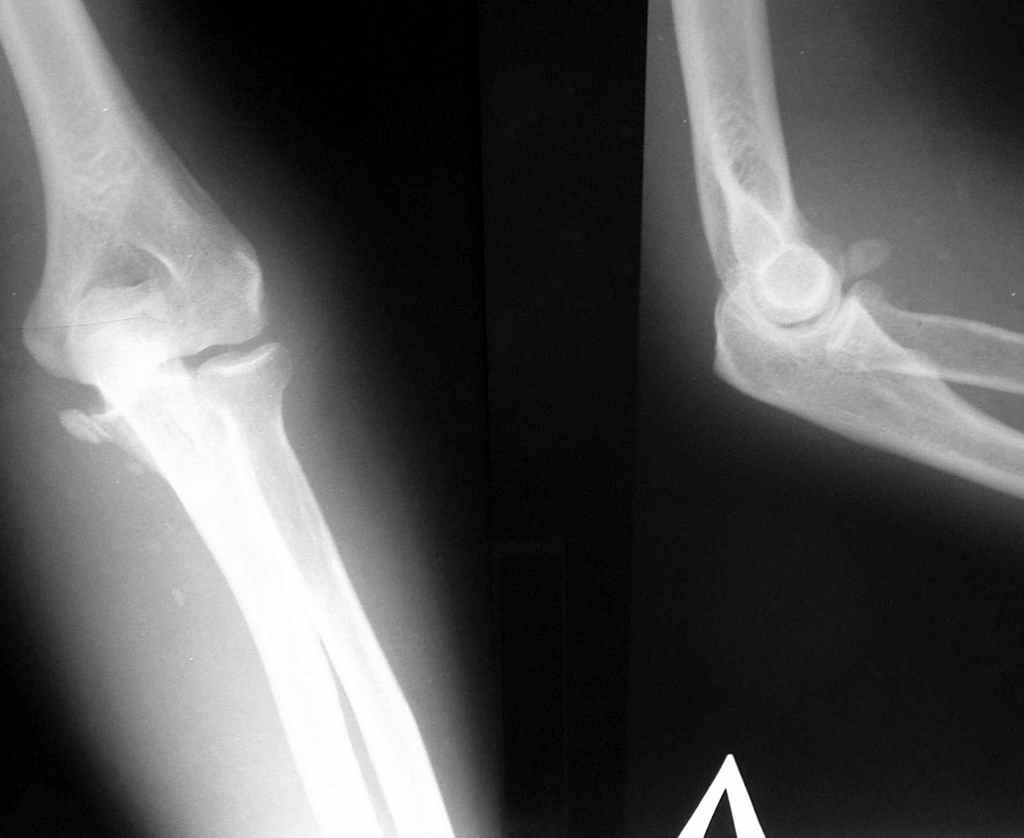

Уважаемые коллеги, 49-летний мужчина во время армреслинга получил травму локтевого сустава.

3 недели лечился в травмпункте с диагнозом отрывной перелом медиального надмыщелка левой плечевой кости (Rtg-1). Лечение состояло в ношении руки на косыночной повязке. Затем в другом учреждении сделали КТ (рис 2,3,4).

Неврологии нет, выраженный отек, активные движения в объеме 60 градусов. Сейчас прошло 4 недели послетравмы.

На R-граммах имеется отрывной перелом внутреннего мыщелка плечевой кости (суставной поверхности). Взаимоотношения в суставе правильные. На КТ - задний вывих предплечья. А не вправляли ли в травмпункте предплечье, не наложив затем гипсовой иммобилизации??? Чтобы предплечье вывихнулось в косынке - ... я не встречал... По тактике - оперативное лечение и чем быстрее, тел лучше. Время идет сейчас не на пользу. Идти задним доступом либо с остеотомией локтевого отростка, либо с V-образным рассечением сухожилия трицепса. Костный свободный фрагмент желательно удалить.

На первичных обычных РГграммах, на мой взгляд, объём информации вполне достаточен - отрывной перелом внутр надмыщелка со смещением фрагмента на

уровень суставной щели - 100процентное показание к оперативному лечению.

Удивлен такими различиями между КТ и Rtg... никогда с таким не встречался. а рентген-снимках никакого намека на вывих не вижу, поэтому и обвинять в халатности персонал травмпункта не стоит. Хотя вполне вероятно, что пальпаторно можно было заподозрить несоответствие обследования с реальной картиной.